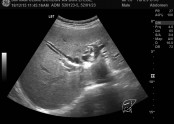

• 췌장에 혹, 간 낭종, 상복부 초음파

• 등록일 2025-12-01 07:38:59

•  복부는 배를 말하는 의학용어입니다.의학용어는 쉬운 말도 어렵게 하지요?상복부라는 뜻은 바꿔 말하면 배의 윗부분을 말하는 것입니다.하복부는 배의 아랫부분이 되겠지요. 왜 복부를 상,하로 나눴을까요?상부에는 간, 쓸개, 췌장, 비장, 신장이라는 장기가 위치해…